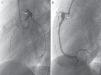

Los controles ambulatorios periódicos incluyeron electrocardiograma, ecocardiografía cada 3-6 meses y TCC cada 12 meses, así como al menos una gammagrafía de perfusión miocárdica (casos más antiguos) o RMDPIV (fig. 3), como prueba de imagen funcional en valoración pronóstica, que se repitió de forma periódica en los 2 casos con trombosis coronaria. Se realizaron coronariografías en los 3 casos más antiguos y en los 2 casos recientes con trombosis intracoronaria, tras pasar la fase inicial de la enfermedad (fig. 4). Se realizó ergometría funcional a los 3 pacientes más antiguos, que fue bien tolerada sin hallazgos patológicos.

El ecocardiograma es la técnica fundamental para el diagnóstico y el seguimiento de las lesiones cardiacas, acompañado del electrocardiograma. De forma rutinaria hoy día, se utiliza la estandarización mediante las tablas de Z-score para clasificar el tamaño de los AC, pues evalúa las dimensiones de las arterias coronarias, ajustada por superficie corporal. Todos nuestros pacientes fueron diagnosticados y seguidos por ecocardiografía; así mismo, las complicaciones fueron valoradas precozmente con esta técnica de imagen. La TCC es una prueba de gran valor en el diagnóstico y el seguimiento de estos pacientes, si bien la exposición a radiaciones ionizantes, la necesidad de anestesia y la regulación de la frecuencia cardiaca son puntos a tener en cuenta: la disponibilidad, la rapidez y la elevada información que proporciona han hecho que se trate de la prueba ideal en sustitución de la coronariografía, que presenta mayores riesgos debido a la fragilidad coronaria de estos pacientes9. Solo se realizó coronariografía en los pacientes más antiguos de la serie, siendo los más recientes estudiados por TCC tanto al diagnóstico como durante el seguimiento. Realizamos TCC de control al año del diagnóstico, salvo que las exploraciones complementarias no invasivas sugieran realización de estudio previo. En cuanto a las pruebas funcionales, la RMDPIV aporta valiosa información sobre la viabilidad miocárdica, además de valorar los aneurismas, en pacientes pequeños precisa sedación y/o anestesia, siendo su punto fuerte la ausencia de irradiación12. La coronariografía define con exactitud aneurismas, estenosis, trombosis con oclusión de la circulación y presencia de circulación colateral. Actualmente, su uso queda limitado a un escaso grupo de pacientes en los que el resto de técnicas de imagen no ha sido contributoria, o bien en aquellos que presentan lesiones crónicas sintomáticas, como terapia de revascularización y en aquellas con obstrucción subclínica y test de isquemia positivos16,17. Solo tienen RMDPIV los pacientes más recientes de la serie, para completar estudio de extensión tras la TCC. Durante el seguimiento, si había lesiones iniciales, se ha realizado un control a los 6 meses y otro al año del primero, y si no hay ningún hallazgo, realizamos la prueba según evolución. En el seguimiento de los pacientes con AC, se recomienda la realización de un ecocardiograma y un ECG cada 2-4 meses; así como un test de detección de isquemia mediante prueba de esfuerzo o RMDPIV cada 6-12 meses o si existe clínica indicativa de isquemia18,19.